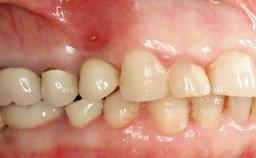

A male patient had lost teeth 11 and 22 as a result of a bicycle accident at age 14. In his adolescent years, a removable prosthesis had replaced the missing teeth. At age 21, the patient was referred by his dentist to the university clinic for treatment of the missing teeth 11 and 22 with implants. He was in good health and a nonsmoker. The absence of teeth 11 and 22 over many years had led to significant atrophy of the alveolar ridge, particularly at site 11. As a first step, the alveolar ridge was augmented using a block graft to replace the lost bone. A Straumann SP implant (diameter 4.1 mm, length 12 mm; Institut Straumann AG, Basel, Switzerland) and a Straumann Narrow Neck implant (length 10 mm) were inserted in the correct location and axial position at sites 11 and 22, respectively, six months later. After three months of healing and subsequent reentry, the patient returned to the referring dentist to receive the prosthetic restoration. The patient was seen again six months after the restoration had been placed. The frontal view showed a high smile line, an irregular gingival profile, and a bluish-gray tinge to implant crowns 11 and 22 compared to the natural dentition.